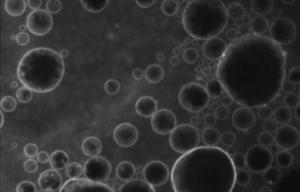

PHARMACOCINÉTIQUE: Des bulles lipidiques pour franchir la barrière hémato-encéphalique